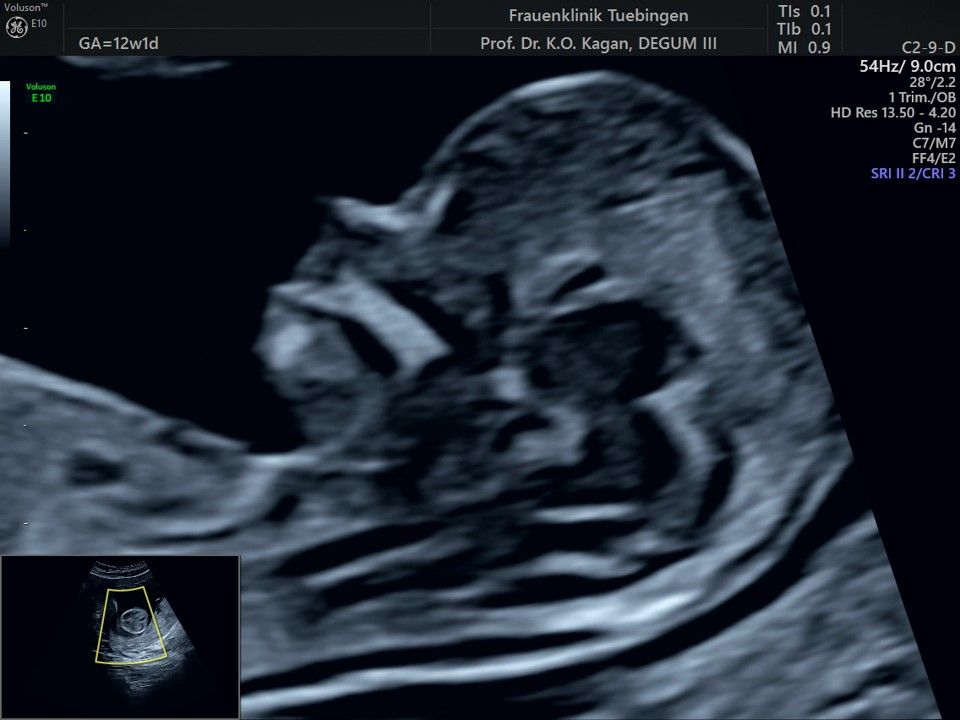

Im Rahmen des Ersttrimester-Screenings untersuchen wir die Organe des Feten mittels Ultraschall. Dabei machen wir auch gerne ein Bild für Sie.

Obwohl der Fet zu diesem Zeitpunkt erst zwischen 5 und 8cm groß ist, lassen sich bereits etwa die Hälfte aller schwerwiegenden Fehlbildungen erkennen bzw. ausschließen. Sollten wir eine Auffälligkeit sehen, werden wir mit Ihnen den Befund und das weitere Vorgehen ausführlich besprechen.

Herz